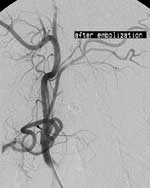

В 70 % случаев удавалось катетеризировать восходящую глоточную артерию тем же самым катетером. В остальных случаях для суперселективной катетеризации использовались коаксиальные микрокатетеры Microferret-18tm калибром 3F производства William Cook Europe. Выполнялась суперселективная артериография, на которой оценивалось полнота кровоснабжения опухоли из данного сосуда, коллатеральное кровообращение, прочность установки катетера. Далее в сосуд вводились эмболизационные агенты. Нами использовались мелконарезанные в спирту частицы гемостатической желатиновой губки, а также частицы поливинилалкоголя калибром 200–500 мкм и металлические и платиновые микроспирали размером 0.018” William Cook Europe. После появления устойчивого стаза в артерии, катетер промывался, микрокатетер удалялся. Основной катетер низводился в наружную сонную артерию и выполнялась контрольная ангиография. При обнаружении дополнительных источников кровоснабжения опухоли выполнялась их катетеризация, ангиография и эмболизация по описанной выше методике. Завершающим этапом являлась каротидная ангиография общей сонной артерии, на которой оценивалась проходимость внутренней сонной артерии, деваскуляризация опухоли (Рис. 3).

[Увеличить]

Рис. 3. Артериография наружной сонной артерии после эмболизации. Опухоль не визулизируется.